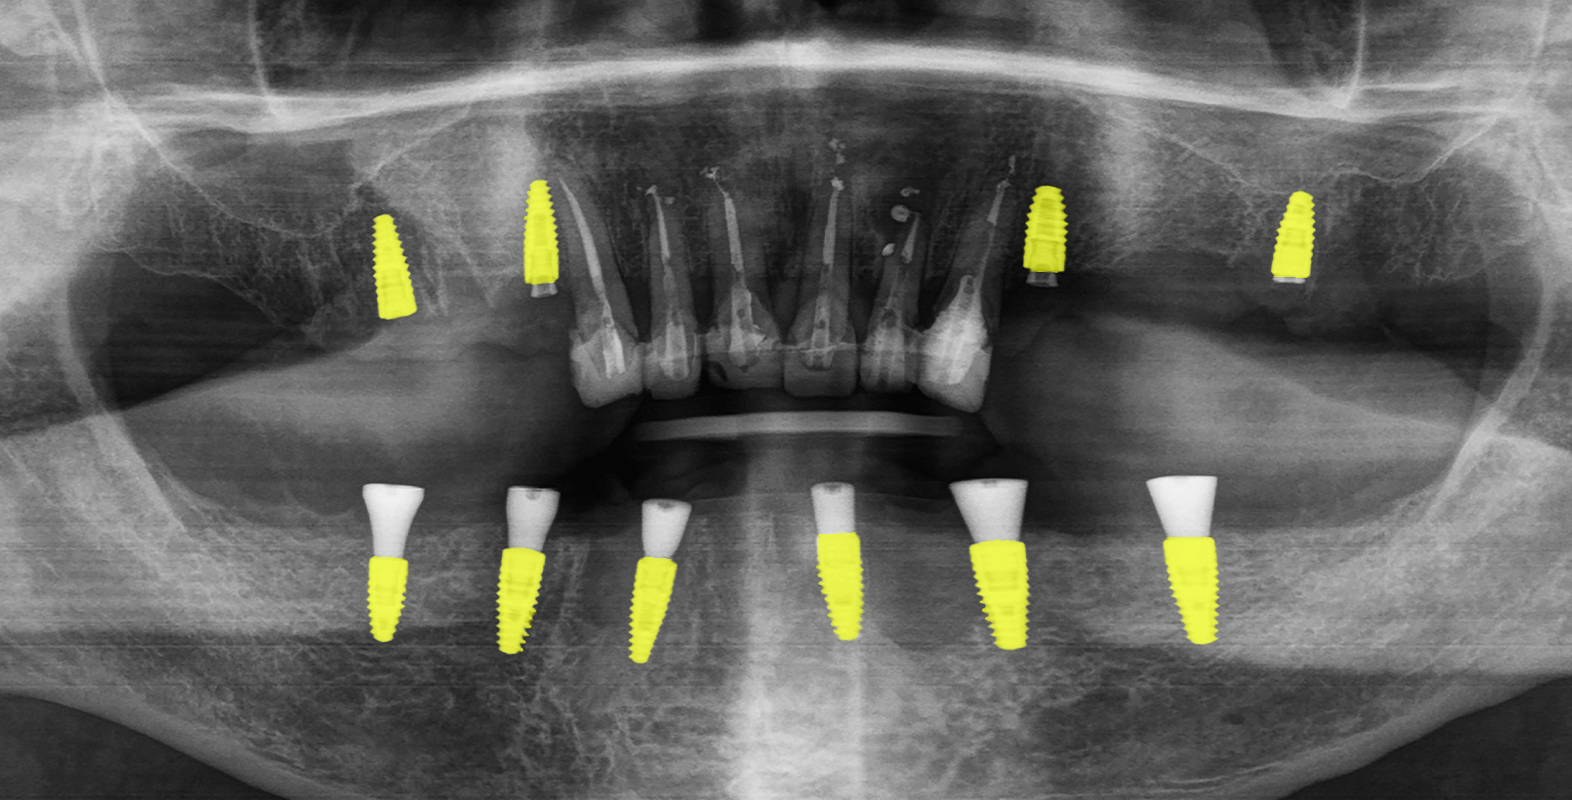

В первый визит врач провел сканирование челюстей пациента, после чего сопоставил данные КТ со сканами в программе по планированию имплантации. Разработал цифровой хирургический шаблон под имплантологическую систему Straumann и напечатал его на 3D-принтере для верхней и нижней челюстей.

За одно посещение врач удалил зубы 1.5, 1.6, 1.7, 2.4, 2.6, 2.7, 4.3, 4.2, 4.1, 3.1, 3.2, 3.3, после чего установил хирургический шаблон и 10 зубных имплантатов: 6 на нижней челюсти. Операция проходила с применением местного обезболивания и продолжалась 1,5 часа.